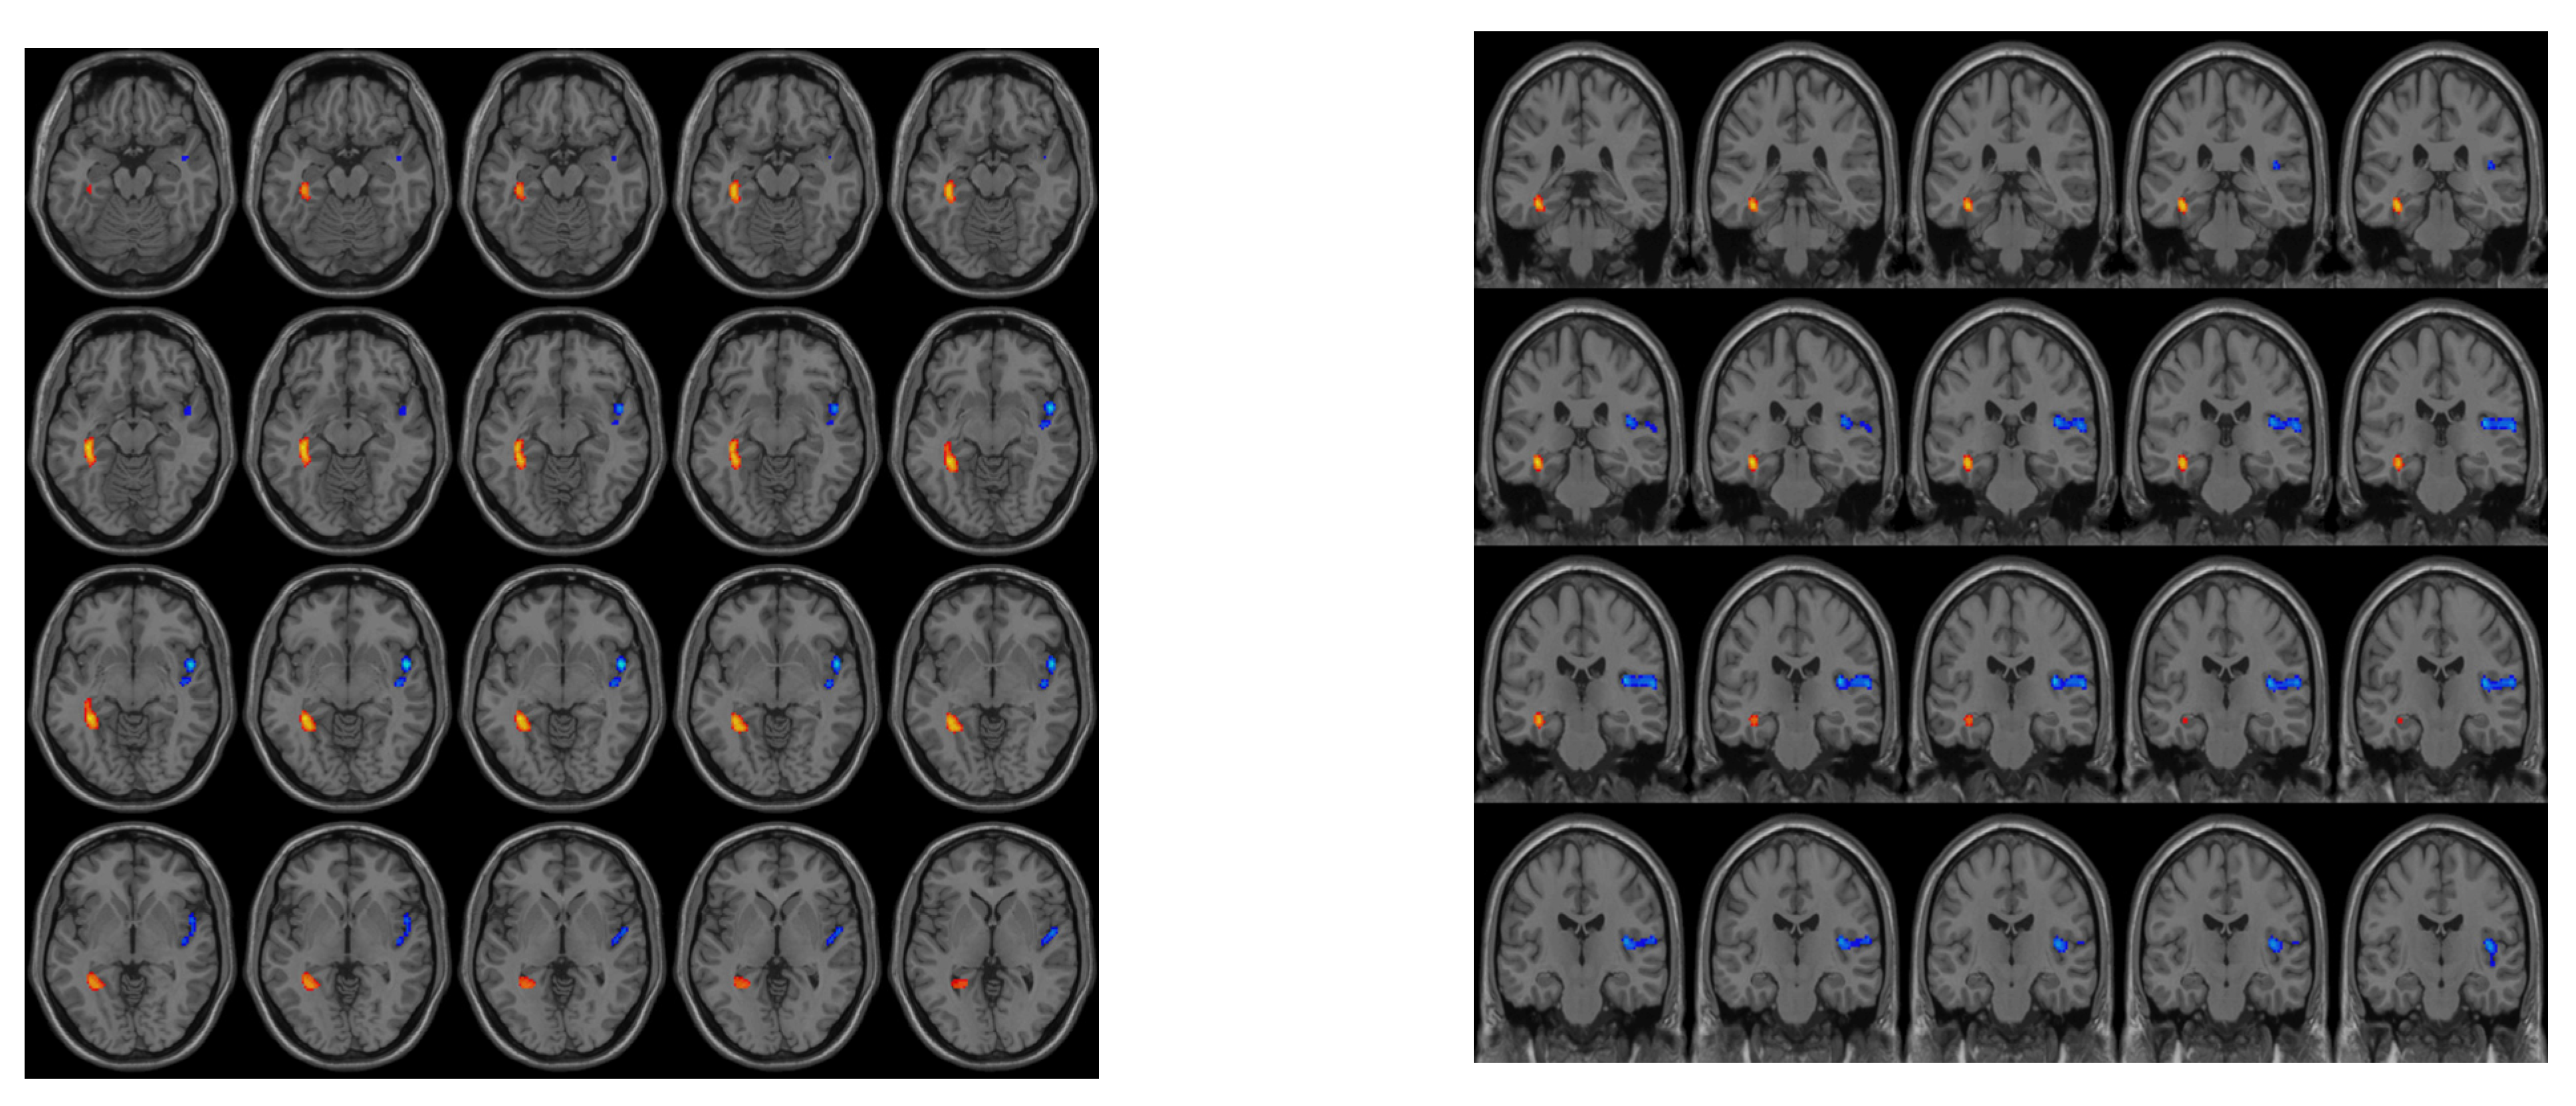

The CKD4 group was found to have decreased CBF in the right insula and increased CBF in the left hippocampus compared to the HC group (Figure 2).

Figure 2.

Differences in CBF between the groups. The CKD4 group was found to have decreased CBF in the right insula and increased CBF in the left hippocampus compared to the HC group.

No brain regions were found to have significant CBF differences between the CKD3 and CKD4 groups or between the CKD3 and HC groups.